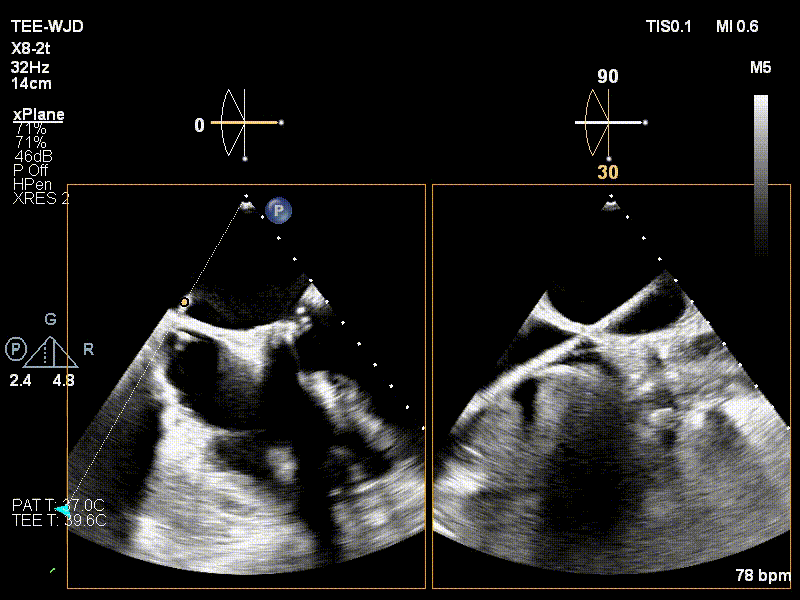

近日,中国医学科学院阜外医院潘湘斌教授团队,在多科室的通力配合下,凭借扎实的手术功底顺利完成一例经导管主动脉瓣和二尖瓣瓣中瓣置换术。

手术过程